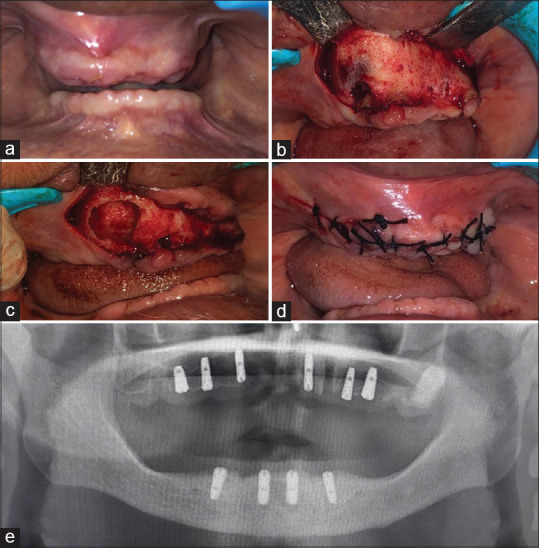

Aim: The study evaluated the ability of chitosan and concentrated growth factors (CGFs) to regenerate bone, grafted into enucleated cystic cavities.

Methodology: The study involved 10 participants, comprising of 3 males and 7 females, with an age range of 18-68 years and a mean of 43 years. Bone regenerative capacity upon implant placement was assessed using radiographic and histomorphometric analyses.

Results: Radiographic and histopathological analyses showed adequate bone filling, bone gain, denser bone, increased trabecular bone area formation, and more compact bone in the test group as compared to control group.